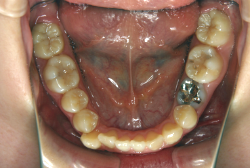

先天性欠如

先天性欠如とは生まれつき永久歯が部分的に欠如している状態をいいます。一般的に下顎前歯や小臼歯が欠如していることが多いです。

「左奥歯でものが噛めない」という主訴で来院したケースです。診断の結果、基本的には「叢生」という隙間が足りないと言うことが原因の凸凹症例でしたが、左下の乳歯が高校生になってもまだ残存している状態で、そのせいで噛み合わせが極端に悪くなっていました。

検査の結果、乳歯の下には後継ぎの永久歯が先天的に欠如していました。配列の凸凹が厳しく非抜歯で矯正することは難しく、仮に無理をして非抜歯治療をしても後々「後戻り」が懸念されることから、このような症例の場合は通常、上下顎左右第一小臼歯を抜歯させていただくのですが、左下は乳歯を抜歯して、第一小臼歯は残すことにしました。これで結果として、小臼歯部を上下左右で一つずつ減らしたのと同じ状況になります。治療後は歯並びが綺麗になっただけでなく、噛み合わせ的にも正しい状態が確立しています。

このように、先天的に永久歯が足りないという症例は最近増えています。親知らずはなくても特に問題になりませんが、その他の歯が足りないと言うのは審美的にも機能的にも重大な障害となります。しかし、矯正治療を正しく行えば、結果として歯がすべてあった場合と全く同じ仕上げにすることも可能です。